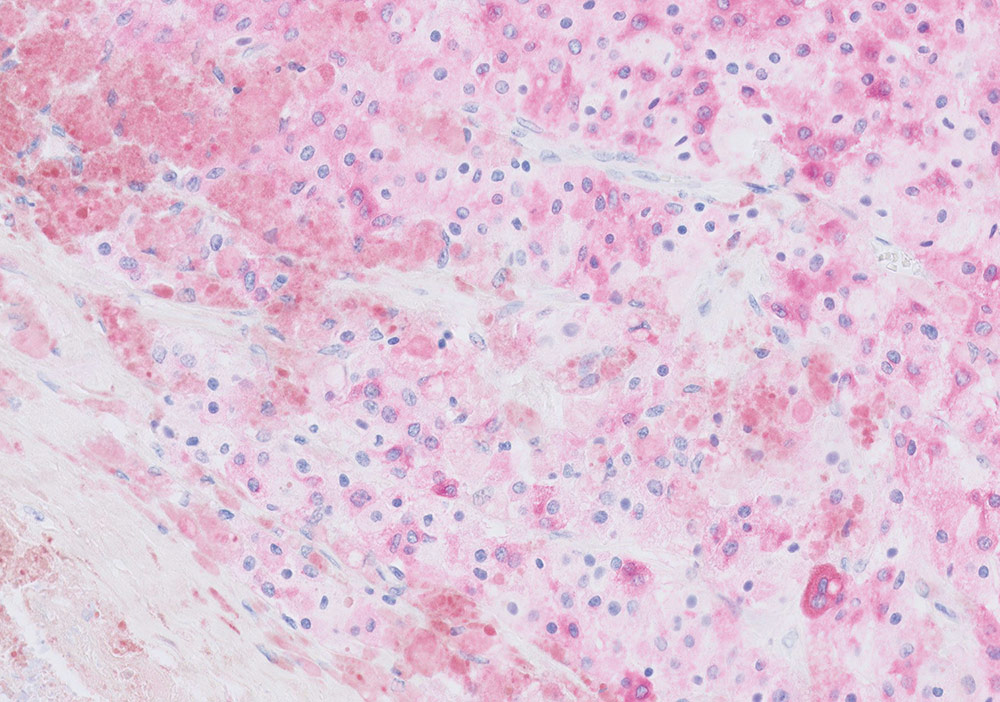

When diagnosing cancer, pathologists typically stain tumor samples with a brown stain called DAB. However, for skin and lung biopsies, they usually choose a red stain as it contrasts well with the brown melanin color in skin, and any pollution artifacts that are typical in lung tissue.

HRP Magenta has a transparent nature, yet is clearly visible, distinct and intense. This allows the pathologist to recognize tissue structures and cellular details even in strongly stained cases. Nuclei can be easily identified, and all details are visible.